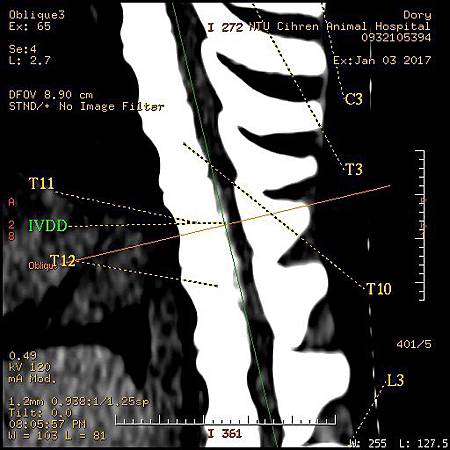

斷層掃瞄 GE Brivo 385 全新16切

本院斷層掃瞄病患

1. 臘腸 IVDD椎間盤突出

3. 臘腸IVDD 椎間盤突出